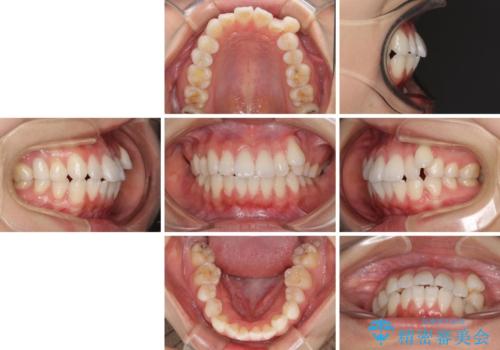

- 八重歯と口元の突出感を気にして来院された患者様です。

歯列が前方に突出しており、上下の正中がズレていたため、左側は上下第一小臼歯を、右側は上下第二小臼歯を抜去し、ワイヤー装置による矯正治療を行うこととしました。

当初はインビザラインによる矯正治療をご希望でしたが、正中を合わせたいことや、口元の突出感を改善したいことから、ワイヤー矯正を強く推奨しました。

治療期間は2年に満たず、スッキリとした口元に仕上がりました。